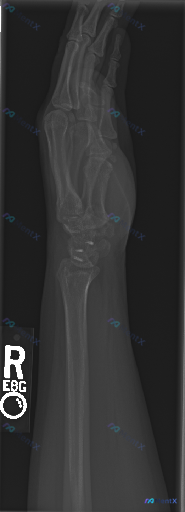

整理到一个影像资料: - 检查类型:右侧(R)腕部及手部侧位X光片 - 影像学描述: - 软组织窗:腕关节掌侧及背侧软组织影显示清晰,未见明显异常增厚、气体影或异物影 - 骨骼:骨皮质边缘尚连续,未见明确的骨折线中断或移位;骨小梁纹理清晰,密度分布大致均匀,未见明显骨质破坏或局限性硬化 - 关节:腕...